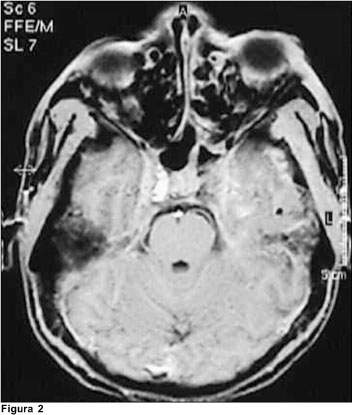

Dos exames de imagem, foram solicitados: tomografia de crânio, que evidenciou assimetria ventricular, às custas de diminuição de ventrículo lateral à direita e tomografia de órbita (Figura 1), que revelou ingurgitamento de veia oftálmica à esquerda. A ressonância de crânio demonstrou redução do fluxo em seio cavernoso à esquerda (Figura 2). A angiores-sonância de crânio demonstrou: redução acentuada do fluxo venoso através do seio transverso esquerdo, sigmóide, seio cavernoso e veia jugular homolateral, correspondendo a trombose nestes segmentos; veias tributárias de convergência apresentavam-se túrgidas e proeminentes (Figura 3).